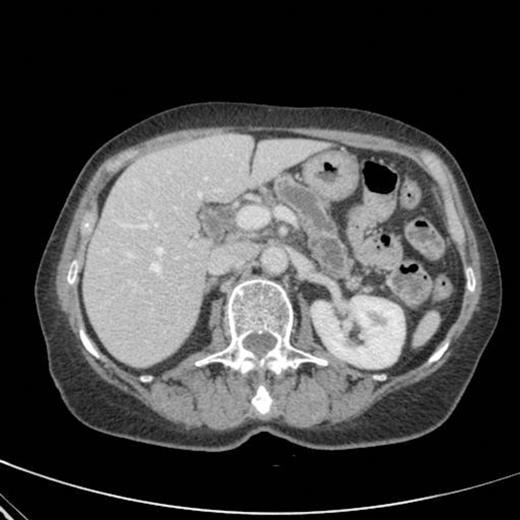

CT scan showing pancreatic duct dilatation to 15 mm with side branch dilatation in uncinate process and atrophic pancreas

CT scan done 2 years later revealed marked dilatation and tortuosity of the main pancreatic duct (12-13mm at the head) with atrophy of the body and tail (Fig1). Repeat scans done on an yearly basis over the next three years reported no progressive change. CT scan done 6 years after the original diagnosis revealed pancreatic duct dilatation to 15 mm with side branch dilatation in uncinate process and atrophic pancreas (Fig 2). A diagnosis of mucinous ductal ectasia or an intraductal papillary mucinous tumour was suggested. On clinical review, patient complained of epigastric discomfort, loose stools, anorexia and weight loss. Upper GI endoscopy and colonoscopy was normal. Faecal elastase was less than 100 confirming pancreatic insufficiency for which she was commenced on creon.